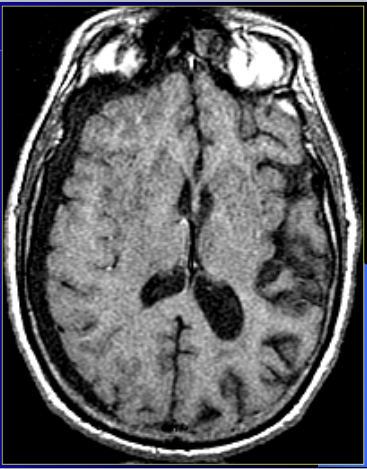

which will be anatomical: T1 or T2?

anatomical = white matter is white, grey matter is grey

T1 is anatomical

Is this T1 or T2?

T-1